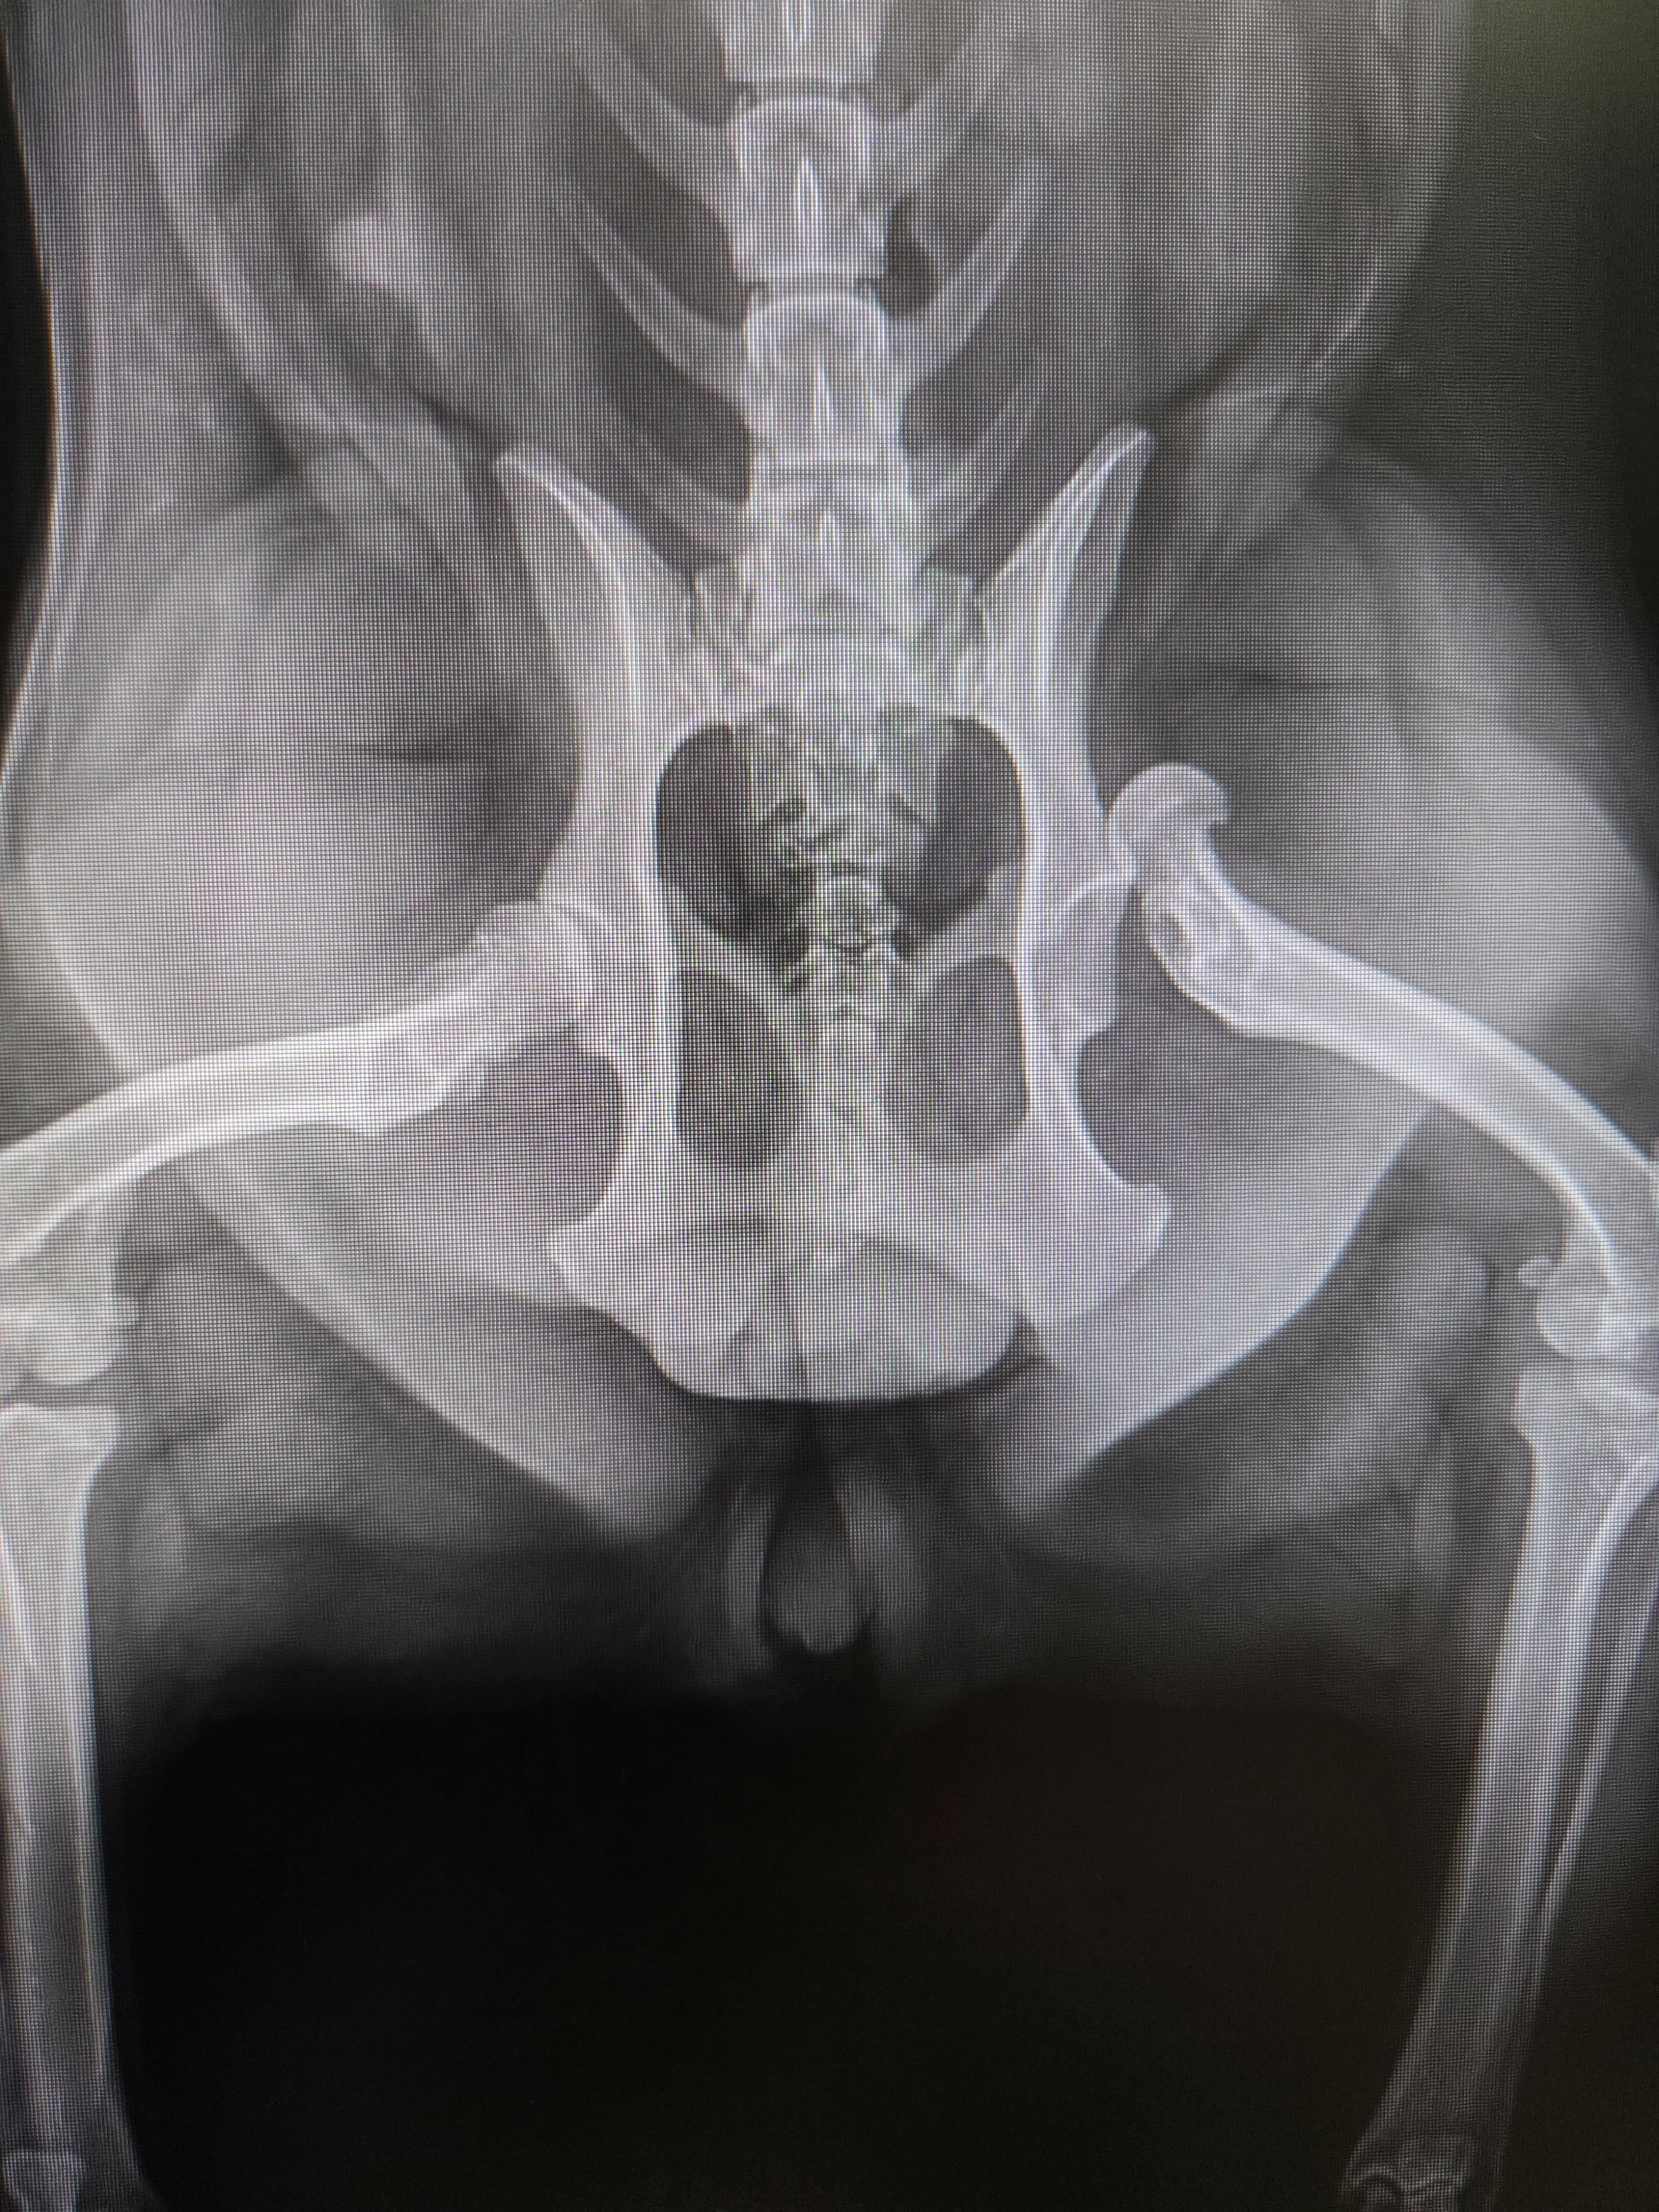

On Saturday, June 7th, Luna was hit by a slow-moving car just outside our house as Michelle and I were prepared to leave. Thankfully, she wasn’t crushed by the wheels, but she was pinned underneath the scorching engine of the low-profile car. She suffered a dislocated left rear hip, multiple burns, scarring across her leg and lips, and a large road rash on her belly. We rushed her to the nearest 24-hour pet emergency clinic, but they were not equipped to handle the complexity of Luna's procedure. At great speed and care, Michelle and I transported Luna to the Central Orange County Emergency Animal Hospital. The amazing doctors tried to reposition her hip and placed her in a SlingWrap to keep it stable.

Unfortunately, her hip did not stay in place, and on Wednesday, June 11th, Luna had to undergo FHO surgery (Femoral Head Ostectomy), where her hip joint was surgically removed.